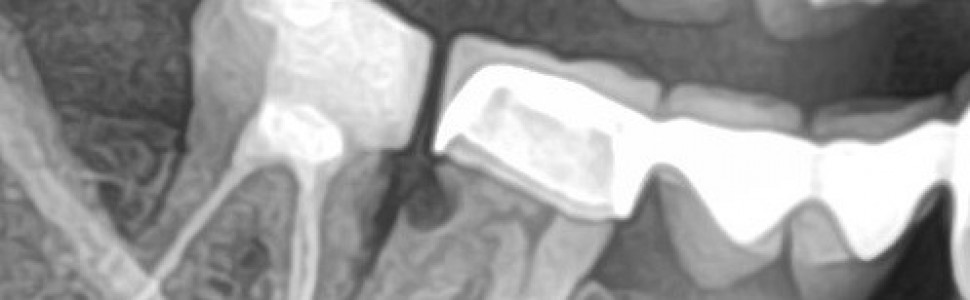

Zastosowanie materiałów bioaktywnych w wypełnieniu ubytku w korzeniu bez zdejmowania mostu protetycznego oraz szybkie gojenie zapalnych zmian okołowierzchołkowych po zastosowaniu uszczelniaczy z bioaktywnej bioceramiki

Artykuł opisuje dwa przypadki wykorzystania materiałów bioaktywnych podczas leczenia. W pierwszym przypadku jest to wypełnienie ubytku w korzeniu materiałem Activa, w drugim – leczenie endodontyczne z użyciem bioceramiki NeosealerFlo.